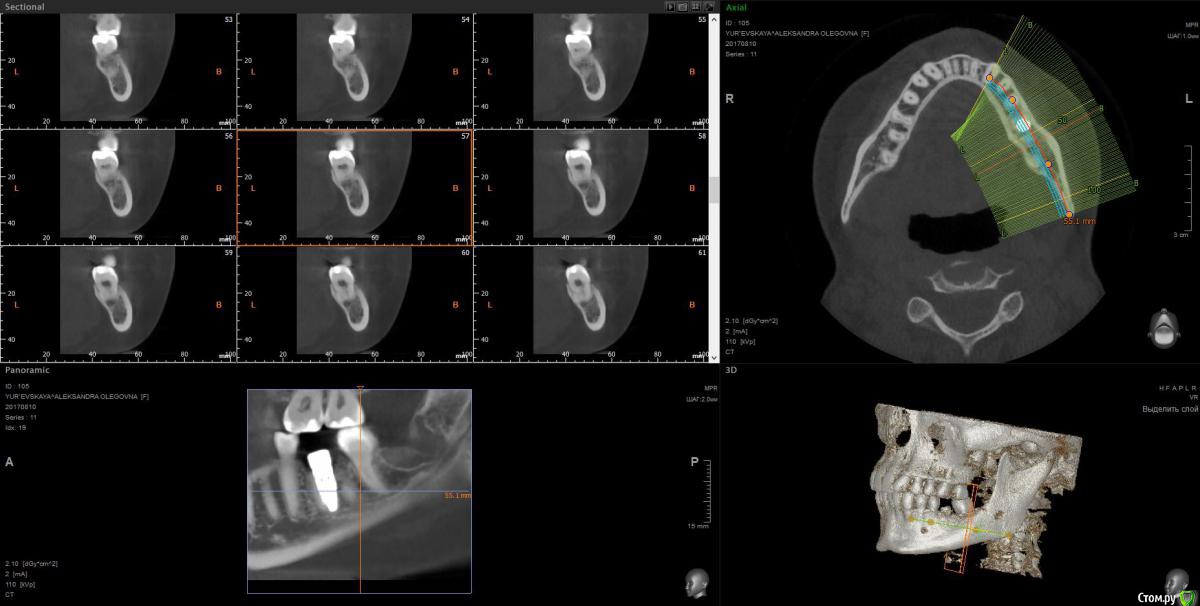

wladdX Опубликовано 28 сентября, 2017 Поделиться Опубликовано 28 сентября, 2017 Ссылка на комментарий

Павел7809 Опубликовано 28 сентября, 2017 Поделиться Опубликовано 28 сентября, 2017 (изменено) А восьмой зуб давно удаляли? Возможно это моя больная фантазия, но покрутив кт я увидел 2 канал нижнечелюстного. Посмотрел еще раз, он там точно есть Изменено 28 сентября, 2017 пользователем Павел7809 Ссылка на комментарий

Kobusha Опубликовано 28 сентября, 2017 Автор Поделиться Опубликовано 28 сентября, 2017 (изменено) А восьмой зуб давно удаляли? Возможно это моя больная фантазия, но покрутив кт я увидел 2 канал нижнечелюстного. Посмотрел еще раз, он там точно естьВосьмерку со стороны имплантата - в мае. Ретинированный зуб был. Нижнечелюстного нерва? а что это значит? =) наличие данного канала? Изменено 28 сентября, 2017 пользователем Kobusha Ссылка на комментарий

Kobusha Опубликовано 28 сентября, 2017 Автор Поделиться Опубликовано 28 сентября, 2017 (изменено) upd. по истории: сходила к имплантологу. Посмотрел кт еще раз(то, которое выше), сделал прицельный снимок. (отдавать или пересылать на почту отказались). ничего не видит. причину боли определить не может, посылает к терапевту. и хочет опять устанавливать временную коронку в ближайшее время(его рабочая версия, что в прошлый раз - коронка люфтила, давая болевой синдром). Но боль-то присутствует.Буду признательна за какие-либо альтернативные точки зрения. Изменено 28 сентября, 2017 пользователем Kobusha Ссылка на комментарий